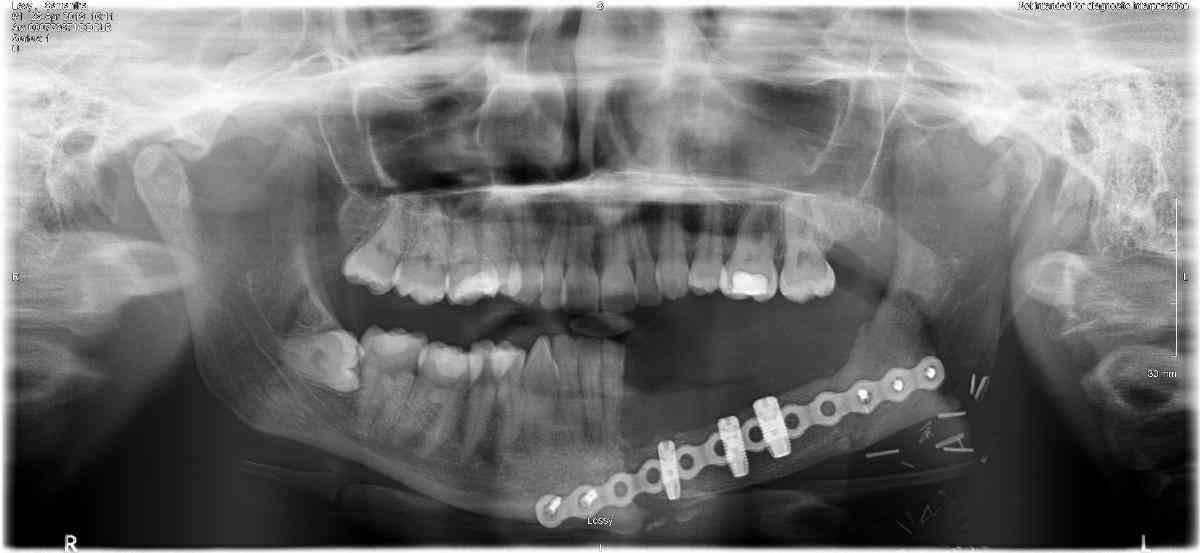

A biopsy confirmed in December 2017 that Sam had a tumour which needed to be removed – it had destroyed the left side of her jaw bone and teeth.

Sam had major surgery on 5 February 2018 to remove the jaw bone and five teeth, and wire her jaw shut.

On 8 March 2018 Sam had a second operation to have her wires removed – but surgeons then discovered they would have to take out more of the jaw and another tooth a month later.

But her worst ordeal was yet to come. During the 11-and-a-half hour marathon June 2018 procedure, bone was cut from her hip and used to rebuild her jaw along with a metal plate. She also had muscles taken from her stomach to replace part of the gum. Doctors had to make a model of her hip and jaw to plan the surgery.

Sam had a final operation in May 2019 to remove the metal plate that held her face in place along the jawline. She said: “I’ve got it at home in a jar! It’s like a badge of honour.”